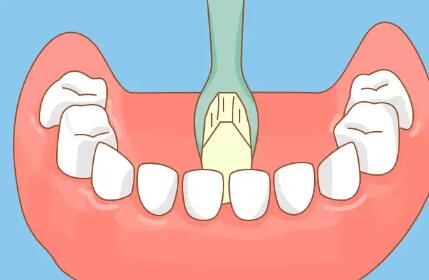

在荥阳市人民医院口腔科,提供一系列先进的口腔修复项目,其中包括一次性牙种植。一次性牙种植是一种常见的修复性牙齿方法,通过这项技术,可以为就诊者恢复丢失的牙齿,让他们重新拥有完整的笑容和咀嚼功能。首先,在进行种植手术之前,医生会进行详细的口腔检查和评估,确定就诊者的口腔健康状况适合进行种植手术。

还会评估就诊者的全身情况,手术一般在局麻下进行,就诊者在手术过程中不会感到太疼或者不适。手术过程中,会先切开牙龈,然后将种植体植入牙槽骨内。种植体植入后,需要进行精细的调整和缝合,确定种植体的稳固性和舒适度。一般来说,种植体与牙槽骨会在3-6个月内紧密结合,经过这段时间后,种植体就可以正常使用了。